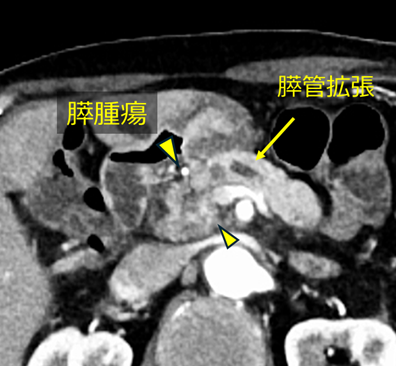

乳癌に対して化学療法を施行中の患者さんで、腹痛のため化学療法の継続が困難となり当院に紹介されました。

CT検査では乳癌の多発膵転移を認め、膵頭部の病変(黄色矢頭)によって主膵管が閉塞し、膵液の流れが障害されていることが示唆されました。